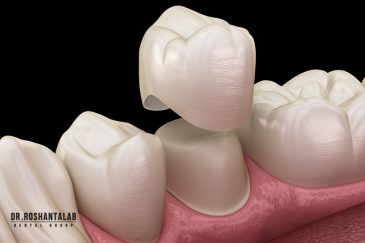

🔸 کاشت ایمپلنت دندان بدون درد

🔸کاشت ایمپلنت فلپ لس یا بدون جراحی و بدون بخیه زیر سه دقیقه

🔸 ایمپلنت دیجیتال و ساخت روکش دیجیتال